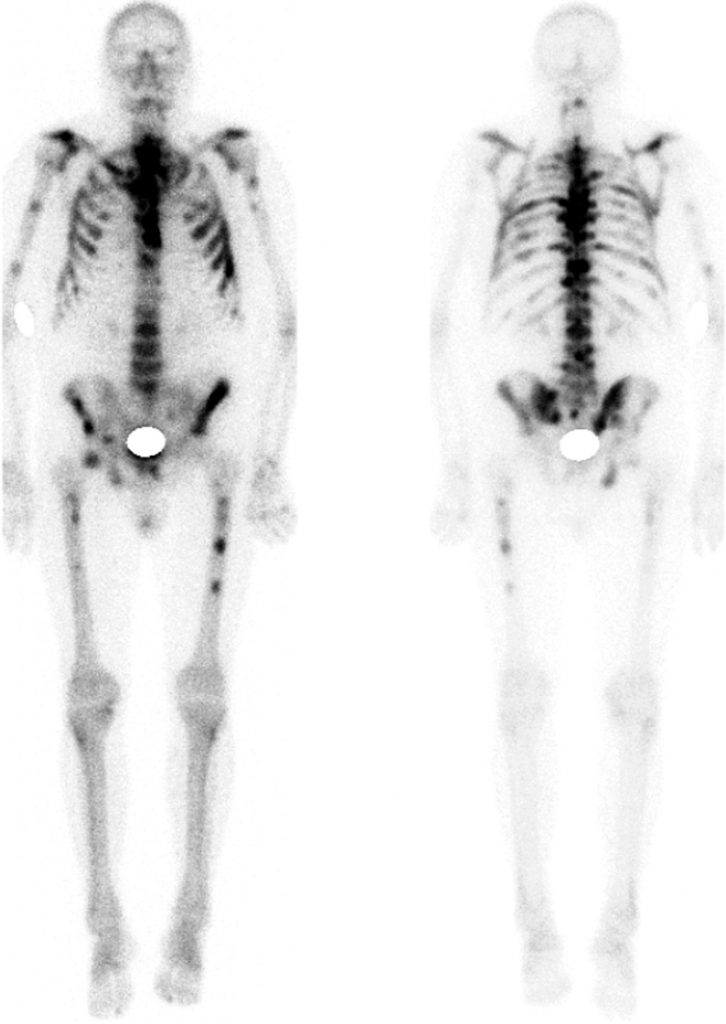

des tumeurs malignes secondaires ostéophiles selon leur composante condensante (scintigraphie osseuse) ou lytique (TEP). Les métastases apparaissent comme des foyers d’hyperfixation associés à d’éventuelles anomalies morphologiques (figure 88.2).

Fig. 88.2 Métastases osseuses d’un cancer prostatique en scintigraphie. Multiples foyers d’hyperfixation sur le squelette axial et périphérique.

Source : CERF, CNEBMN, 2022.